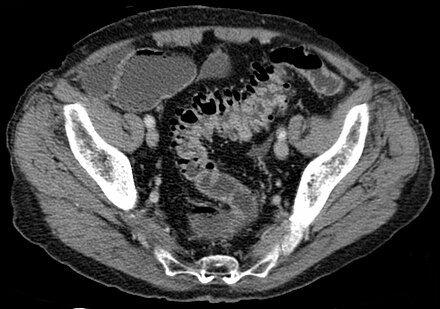

CT scan

A computerized tomography (CT) scanExternal NIH Link uses a combination of x-rays and computer technology to create images of your gastrointestinal (GI) tract.

An x-ray technician performs the procedure in an outpatient center or a hospital. A radiologist reads and reports on the images. You don’t need anesthesiaExternal NIH Link for this procedure.

For a CT scan, a health care professional may give you a solution to drink and an injection of a special dye, called contrast medium. Contrast medium makes the structures inside your body easier to see during the procedure. You’ll lie on a table that slides into a tunnel-shaped device that takes the x-rays. A CT scan of your colon is the most common test doctors use to diagnose diverticulosis and diverticulitis.